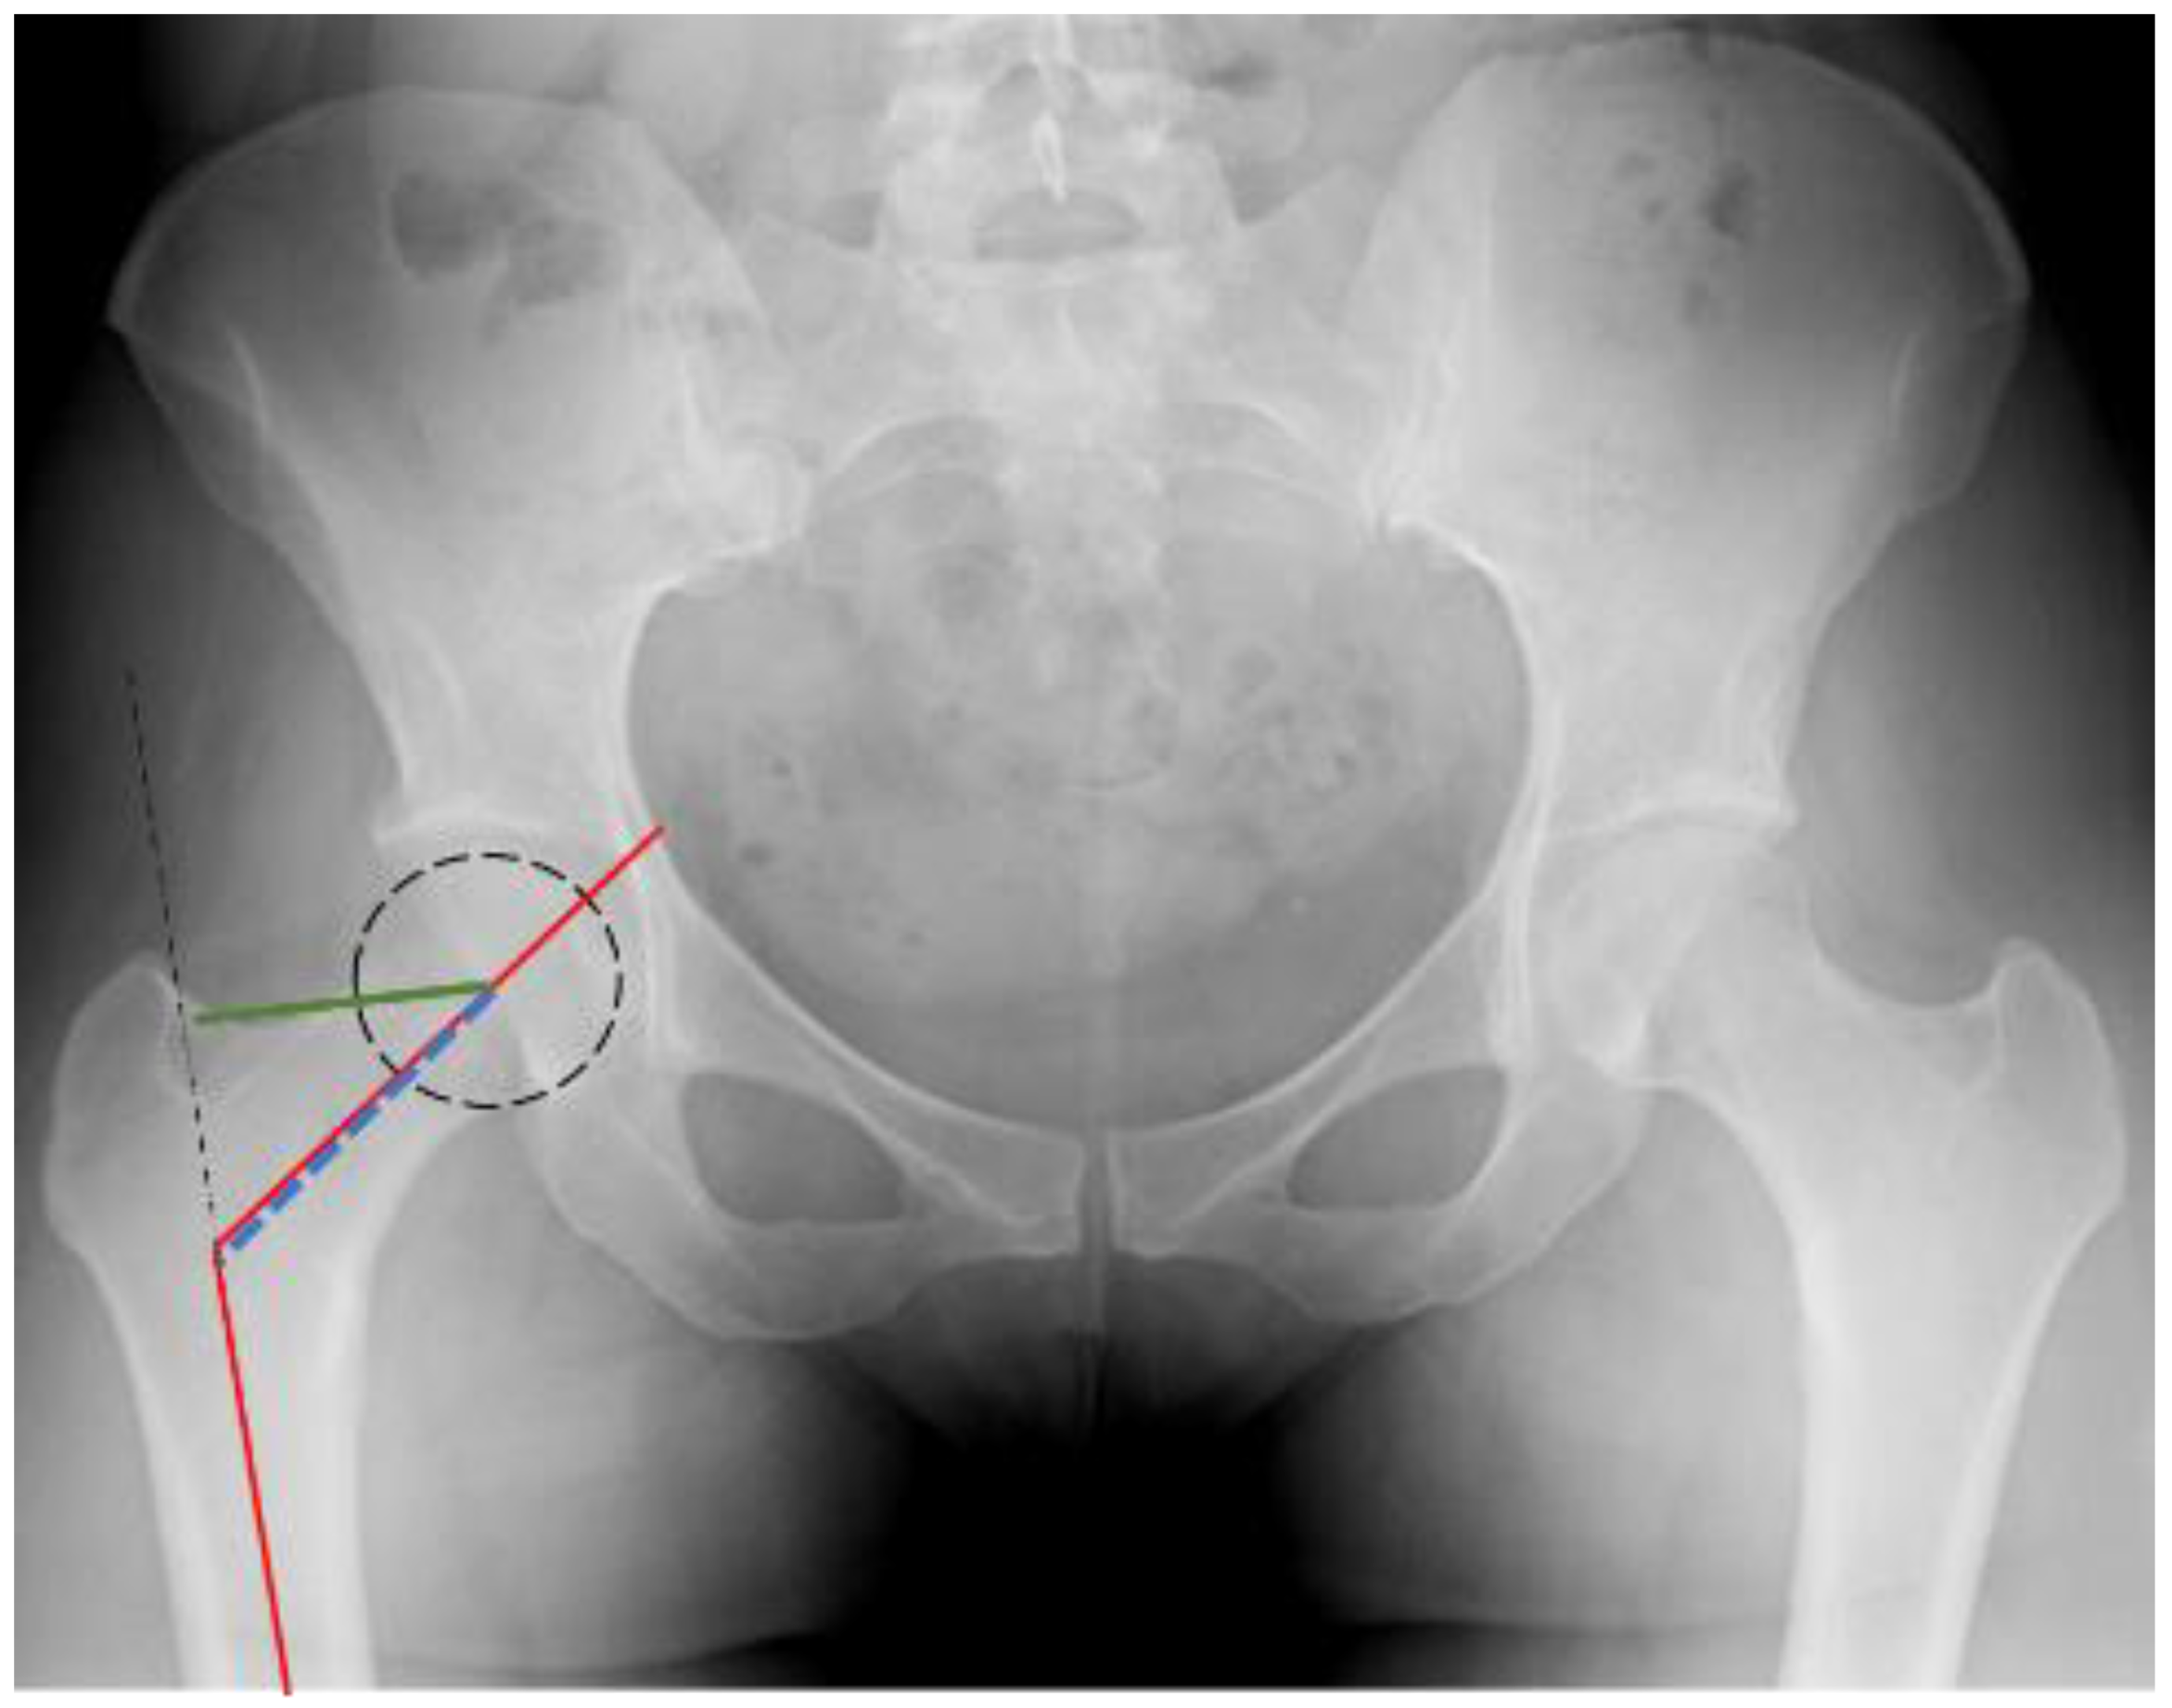

2.2. Measurement Parameters

| Femoral Head Diameter (FHD) | 5.4 | 0.4 | |

| Femoral Neck Diameter (FND) | 3.8 | 0.4 | |

| Femoral Shaft Diameter (FSD) | 3.1 | 0.3 | |

| Femoral Canal Diameter (FCD) | 1.6 | 0.3 | |

| Offset Length (OL) | 3.8 | 0.7 | |

| Neck Length (NL) | 5.2 | 0.8 | |

| Neck Shaft Angle (NSA) | 132.1 | 5.1 | |

| Wiberg Angle (WA) | 44.9 | 8.1 | |

| Acetabular angle (AA) | 34.6 | 3.8 | |

| Hip Axis Length (HAL) | 11 | 0.9 |